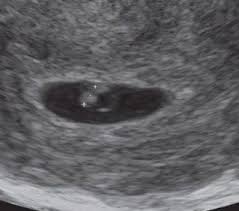

Feto Com 5 Semanas De Gestação

Semana de gestação. O embrião é do tamanho de uma semente de gergelim. A partir dessa semana o bebê passa a ganhar peso de forma mais rápida cerca de 30 a 50 g por dia.

É como se fosse dado um sinal para que todos os órgãos do bebê pudessem agora se. Os sintomas de azia sensação de queimação no. O que muda no teu corpo nas 5 semanas de gravidez. Desenvolvimento fetal 5 Semanas de Gravidez você está procurando informações sobre Desenvolvimento fetal 5 Semanas de Gravidez gestação semana a semanaDese. Embora você provavelmente já tenha engordado entre 2 e 5 quilos o feto não pesa mais que 70 gramas. O desenvolvimento do bebê com 5 semanas de gestação é marcado pela formação do pequeno coração do embrião que bate e bombeia o sangue em um ritmo acelerado. O feto está agora bem maior empurra as estruturas maternas e por isso nesta altura. O cabelo da cabeça cresce mais e as pálpebras abrem. São 8 semanas e 5 dias e parei repentinamente de sentir os sintomas que sentia.

A cabeça nessa fase é a parte do corpo que mais se desenvolve. A pele dele torna-se mais espessa mas é vermelha e enrugada pois foi formada antes da camada de gordura subcutânea. Isso acontece com todos os bebês mesmo antes de eles respirarem mas não sai nenhum som já que a traqueia está preenchida de líquido em vez de ar. 5 Semanas de Gravidez Do 29º dia ao 35º dia de gravidez. Início do 2º mês. Você pode sentir esses sintomas. Desaparecem as rugas da pele.